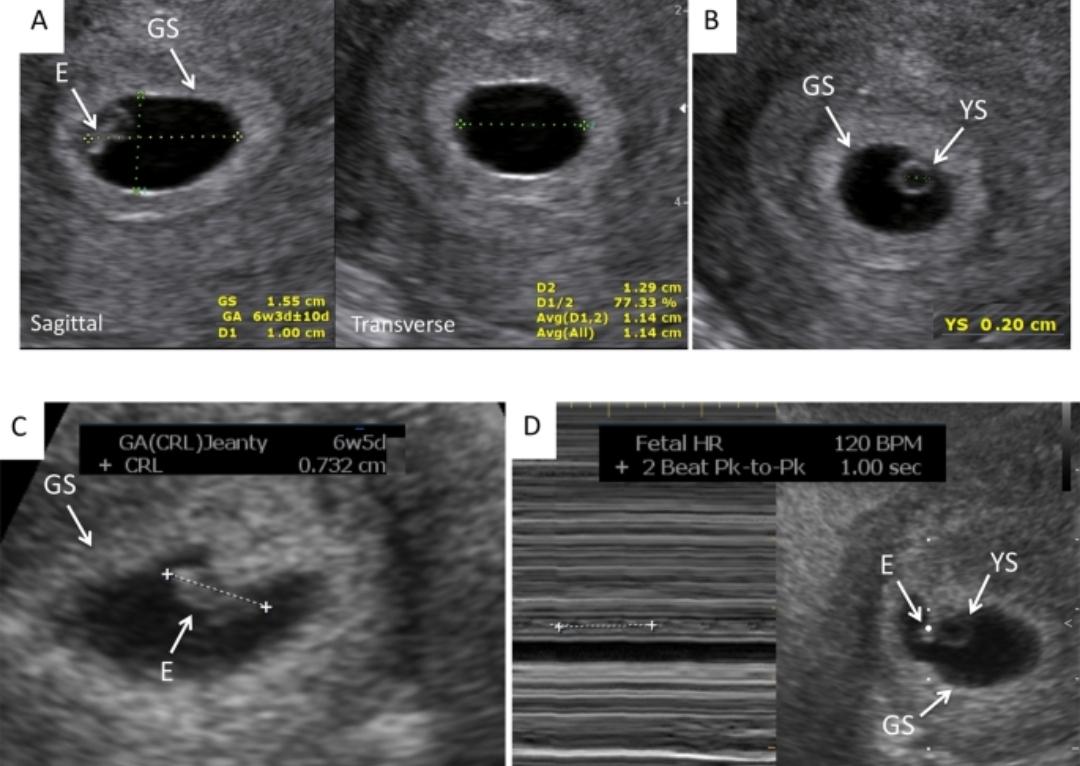

일반적으로 질초음파에서 아기집이 약 8~10mm 전후가 되면 난황이 보이기 시작하는 경우가 많지만, 이는 평균적인 기준일 뿐 절대적인 기준은 아닙니다. 실제로 10mm 이상에서도 며칠 늦게 난황이 확인되는 경우가 있고, 특히 배란일이 정확하지 않은 경우에는 더 그렇습니다. 아기집이 먼저 커지고 이후 난황, 태아로 발달 속도가 맞춰지는 경우도 임상에서 흔히 관찰됩니다.

Ovum blight(무배아 임신)는 보통 아기집이 20~25mm 이상으로 커졌음에도 난황이나 태아가 전혀 보이지 않을 때 진단을 고려합니다. 현재 아기집 크기(약 9mm) 단계에서는 예후를 판단하기에 너무 이른 시점입니다. 이 시기에 난황이 안 보인다고 해서 바로 예후가 나쁘다고 보지는 않습니다.